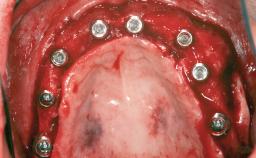

Iliac and Calvarial Bone Blocks for Onlay Grafting of a Severely Resorbed Edentulous Maxilla

A 45-year-old woman with a completely edentulous maxilla was referred to evaluate the possibility of rehabilitation with an implant-supported prosthesis. This patient was healthy and a non-smoker. She had been wearing a maxillary complete denture opposing a natural mandibular dentition since her twenties. This situation had resulted in progressive resorption of the alveolar ridge, repeatedly creating a need for relining the denture. Twenty years later, despite multiple adaptations and the use of “glues” the denture was unstable and causing the patient psychological and functional discomfort.

# of Implants 8

Type of Implants Reduced-Diameter|Two-Piece